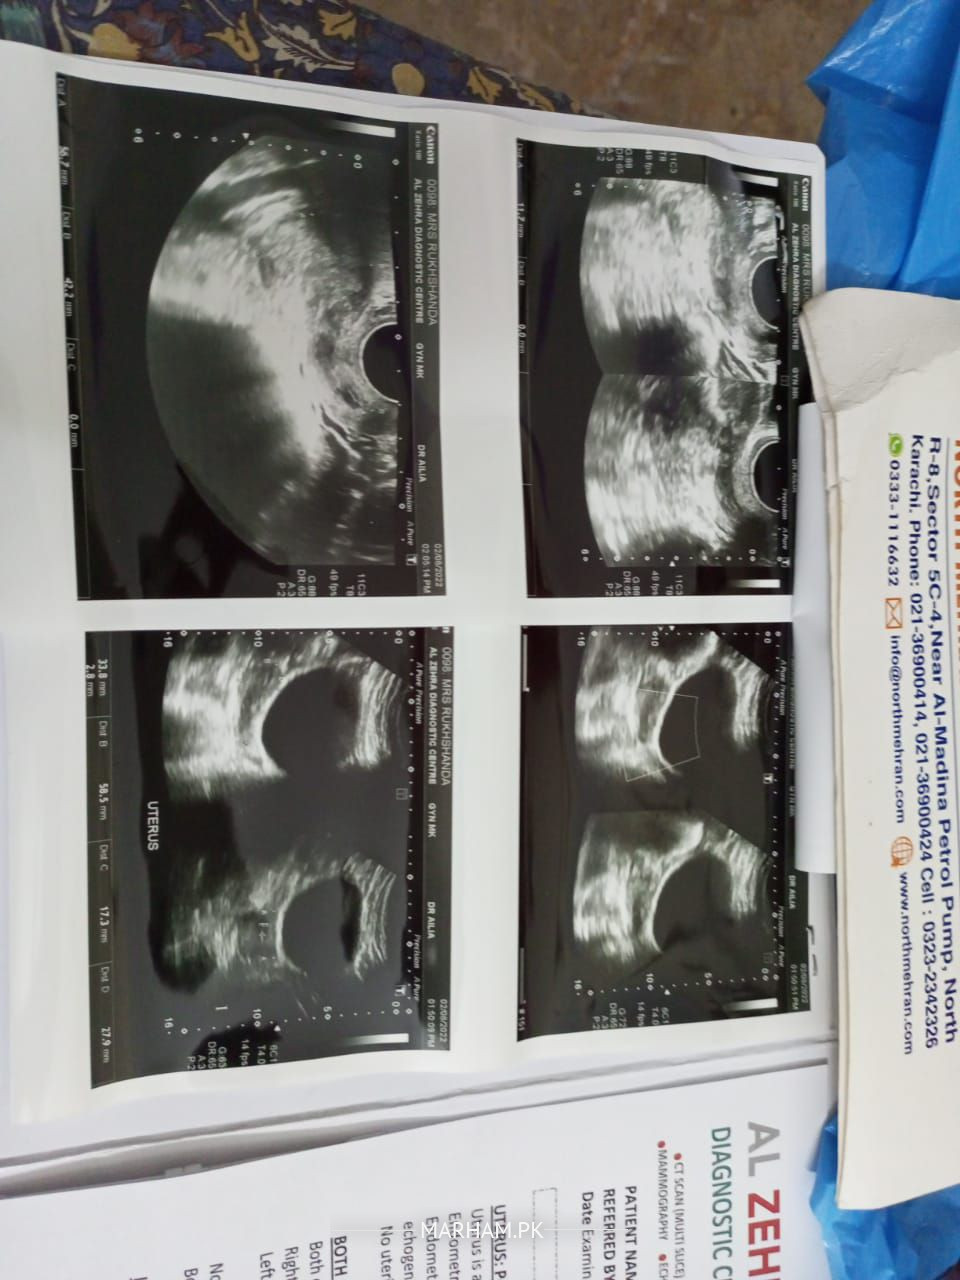

Hey can any gynaecologist please comment on this U/S report. TIA

patient age? she is having postmenopausal bleeding?

Suspicion of uterine cancer. Consult gynaecologist soon.